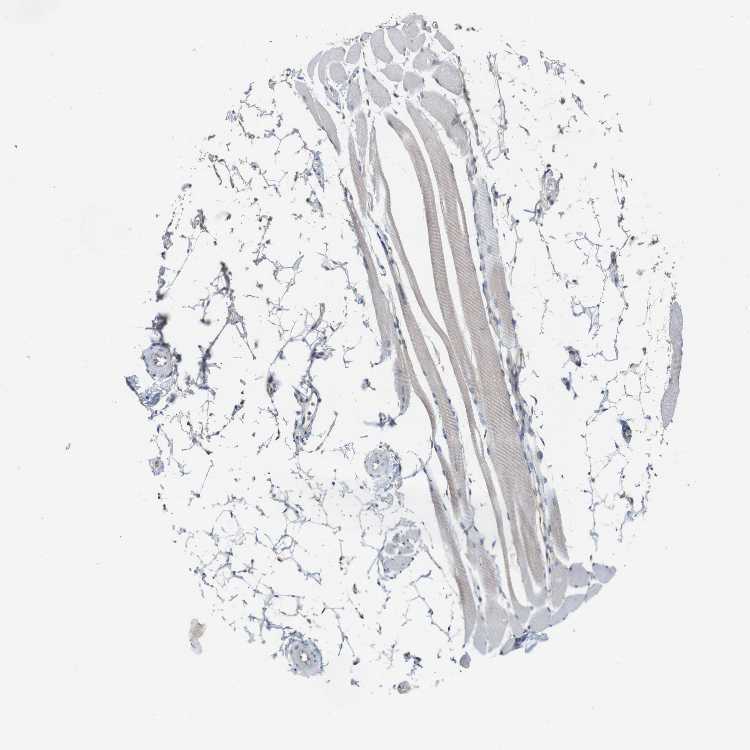

TISSUE PRIMARY DATA SKELETAL MUSCLE Show tissue menu

SKELETAL MUSCLE - Antibody stainingi

Antibody staining in the annotated cell types in the current human tissue is reported as not detected, low, medium, or high, based on conventional immunohistochemistry profiling in selected tissues. This score is based on the combination of the staining intensity and fraction of stained cells.

Each image is clickable and will lead to virtual microscopy that enables deeper exploration of all samples and also displays staining intensity scores, fraction scores and subcellular localization as well as patient and tissue information for each sample.

Antibody HPA002642Antibody CAB009008

Myocytes Not detectedNot detected